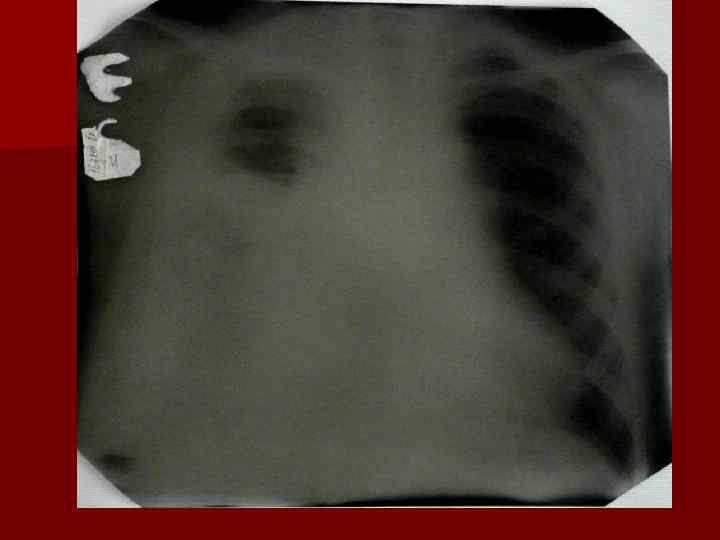

Пневмония Воспалительный процесс в респираторных отделах легкого с наличием внутриальвеолярной экссудации. n Это острое инфекционное заболевание легочной паренхимы, диагностируемое по синдрому дыхательных расстройств и/или физикальным данным при наличии очаговых или инфильтративных изменений на рентгенограмме. n Пневмония – это, прежде всего, клинический диагноз, который ставит врач у постели больного, и только затем подтверждает рентгенологически. n

Пневмония - это неспецифическое воспаление легочной ткани, в основе которого лежат инфекционный токсикоз, дыхательная недостаточность, водно – электролитные и прочие метаболические нарушение с патологическими изменениями во всех органах и системах детского организма. Заболевание диагностируется на основании синдрома дыхательных расстройств и/или физикальных данных и верифицируется рентгенологически выявлением инфильтративных изменений в легких.

Долевая пневмония характеризуется лобарным пневмоническим инфильтратом. Крупозная ( пневмококковая) пневмония диагностируется прежде всего по клиническим данным. Крупозная пневмония сохраняет свою типичную картину пневмококковой пневмонии: острое начало с характерными клиническими данными, циклическое течение, несклонность к деструкции, гомогенной и лобарной инфильтративной тенью при рентгенологическом исследовании. Вместе с тем, широкое использование антибиотиков способствовало значительному снижению числа крупозных пневмоний у детей. Интерстициальная – редкая форма пневмоний, при которой оказывается поражен прежде всего интерстиций. Как правило, интерстициальная пневмония обусловлена вирусами, пневмоцистами, внутриклеточными микроорганизмами и грибами.

Морфологическую форму пневмонии определяют по клинико – рентгенологическим данным: выделяют очаговую, очагово – сливную, долевую ( крупозную), сегментарную и интерстициальную пневмонии. Очаговая – наиболее распространенная форма. Пневмонические очаги чаще бывают размером 1 см и более. Очагово – сливная – инфильтративные изменения в нескольких сегментах или во всей доле легкого, на фоне которых могут быть видны более плотные участки инфильтрации и/или полости деструкции. Сегментарная – в процесс вовлекается весь сегмент, который, как правило, находится в состоянии гиповентиляции, ателектаза. Морфологическая картина воспаления при очаговых и сегментарных пневмониях связана с первичным инфекционным воспалением в бронхах, что дает основание отнести эти варианты поражения легочной ткани к бронхопневмониям, нередко сопровождающихся бронхообструктивным или бронхообтурационным синдромами. В настоящее время данный тип пневмоний у детей встречается наиболее часто.